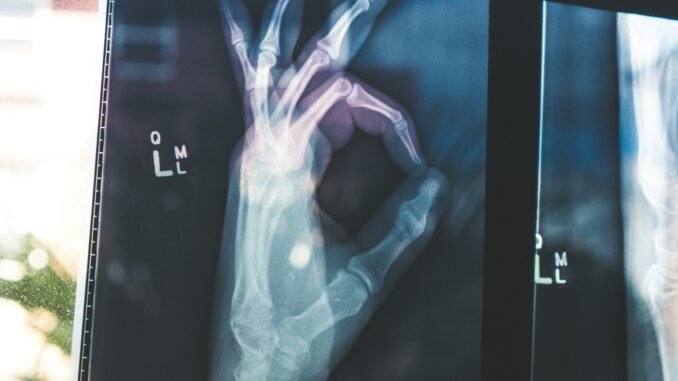

The flagship MedGemma 27B model doesn’t just read medical text like previous versions did; it can actually “look” at medical images and understand what it’s seeing. Whether it’s chest X-rays, pathology slides, or patient records potentially spanning months or years, it can process all of this information together, much like a doctor would.

(Photo by Owen Beard)